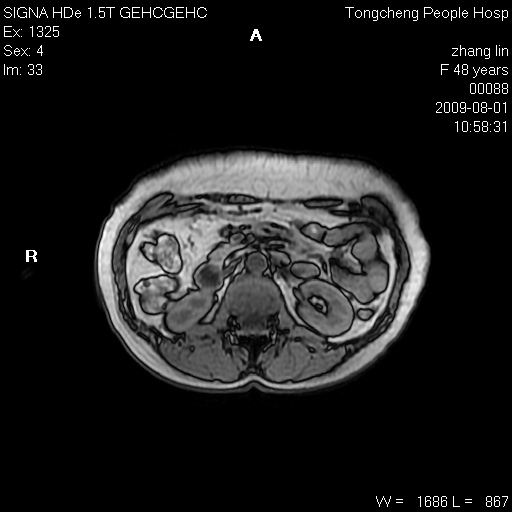

女,48岁。健康体检,彩超发现右肾占位性病变。平素健康。

临床诊断:右肾占位性病变,性质待定(囊肿?肿瘤?)。

上中腹部mr平扫+增强扫描,图像如下:

右肾上极见一类圆形病灶,t1wi呈等信号t2wi呈等高混杂信号,三期增强无强化,边界清---考虑囊肿出血。